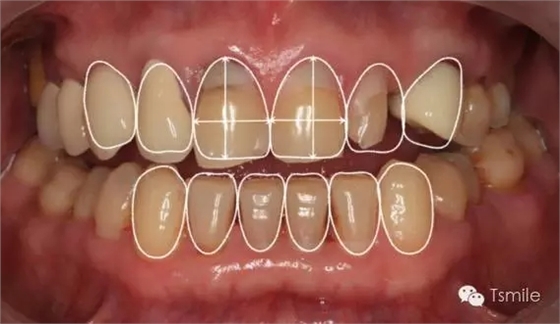

美學(xué)表達(dá)就是要把醫(yī)師大腦中形成的美學(xué)設(shè)計(jì)思想,采用各種方法準(zhǔn)確、真實(shí)、直觀地表達(dá)給患者,進(jìn)行醫(yī)患溝通,進(jìn)行口內(nèi)診斷性美學(xué)修復(fù)。在口內(nèi)根據(jù)患者主客觀反應(yīng)進(jìn)行調(diào)改,形成最終的美學(xué)修復(fù)設(shè)計(jì)。最后進(jìn)行醫(yī)技溝通,指導(dǎo)技師完成修復(fù)體制作。美學(xué)表達(dá)的方法有:數(shù)碼圖像設(shè)計(jì)(如DSD)、診斷飾面(Mock-up)、診斷蠟型(Wax-up)、模型外科、臨時(shí)修復(fù)體等。

例如面對一個(gè)牙列重度磨耗的美學(xué)修復(fù)患者,我們首先根據(jù)患者主訴和美學(xué)檢查形成美學(xué)設(shè)計(jì),然后通過數(shù)碼圖像表達(dá)美學(xué)設(shè)計(jì)思想,制作診斷蠟型,口內(nèi)制作診斷飾面,更加真實(shí)地表達(dá)美學(xué)設(shè)計(jì)。根據(jù)患者的要求和口內(nèi)試戴情況調(diào)改診斷飾面,最終確定美學(xué)修復(fù)設(shè)計(jì),即最終修復(fù)體的各種美學(xué)參數(shù)。接下來就是美學(xué)實(shí)現(xiàn)過程,在診斷飾面上進(jìn)行精確地牙體預(yù)備,制取印模和工作模型,技師按照最終診斷飾面的形態(tài)、大小和排列制作最終美學(xué)修復(fù)體,最后完成修復(fù)體粘接。

在前牙的美學(xué)分析中有四個(gè)最重要的美學(xué)影響因素,稱之為前牙美學(xué)四要素。包括上中切牙切緣的位置、上中切牙臨床冠的寬長比、上中切牙齦緣的位置、上前牙的寬度比例。這四要素是影響前牙美學(xué)的主要因素,根據(jù)這四要素就可以簡單、快速、準(zhǔn)確地分析患者前牙存在的美學(xué)缺陷。根據(jù)這四因素就可以準(zhǔn)確、直接地進(jìn)行患者前牙的美學(xué)修復(fù)設(shè)計(jì)。